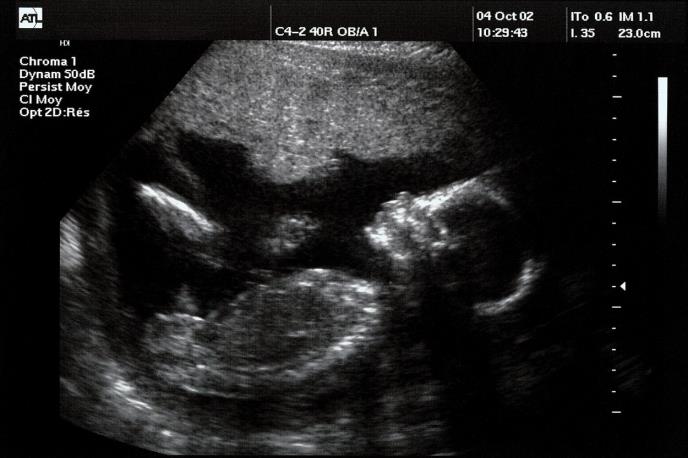

Novo istraživanje pokazalo je da bebe mogu da prepoznaju ljudska lica dok su još u materici.

Koristeći izvor svetlosti da projektuju tri tačke u formaciji očiju i usta kroz zid materice, istraživački tim je primetio da će se bebe od čak 34 nedelje okrenuti ka projekciji.

U istoj situaciji sa tri tačke u obilku trougla nisu dobijeni takvi rezultati, što sugeriše da nije svetlost, već oblik ono što privlači bebinu pažnju.